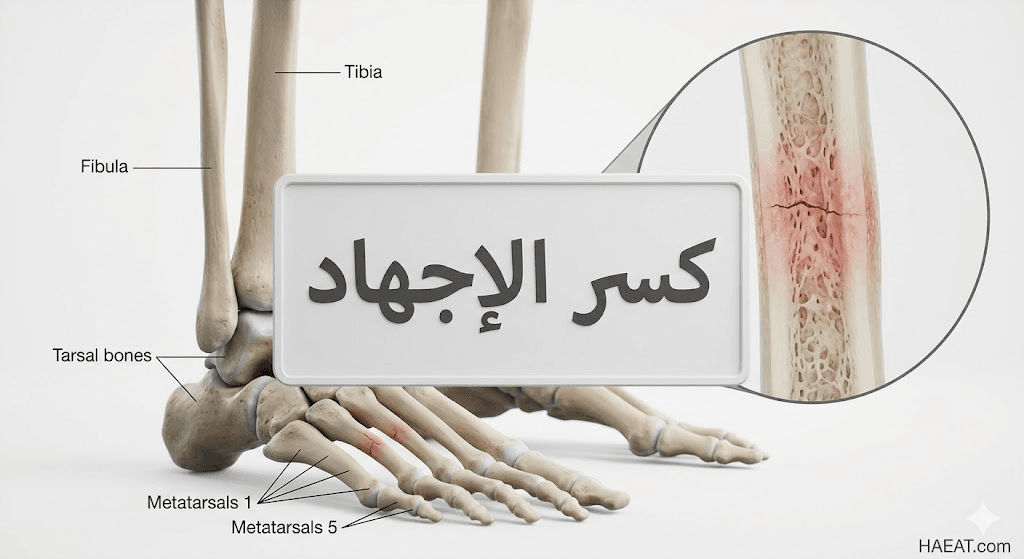

يُعد كسر الإجهاد (Stress fracture) من أكثر الإصابات الرياضية شيوعاً التي تستهدف العظام نتيجة التحميل الزائد والمتكرر، وهو يختلف جذرياً عن الكسور الحادة الناتجة عن السقوط المفاجئ.

تؤكد “مدونة حياة الطبية” أن هذه الإصابة العظمية تبدأ كشقوق مجهرية صغيرة لا يمكن رؤيتها أحياناً بالأشعة التقليدية في مراحلها الأولى، مما يتطلب وعياً طبياً عميقاً بآلية حدوثها لتجنب تفاقم الحالة.

يُعرف كسر الإجهاد طبياً بأنه كسر شعري دقيق يحدث في العظم نتيجة تعرضه لقوى فيزيائية متكررة تفوق قدرته الطبيعية على التحمل والترميم الذاتي المستمر.

بناءً على ذلك، يظهر كسر الإجهاد غالباً في العظام التي تحمل وزن الجسم الأساسي، مثل عظام مشط القدم، وعظمة الساق (الظنبوب)، وعظمة العقب، نتيجة الأنشطة التي تتضمن القفز أو الجري لمسافات طويلة.

يتطلب تشخيص كسر الإجهاد دقة بالغة نظراً لأن الشقوق الصغيرة غالباً ما تكون غير مرئية في المراحل المبكرة باستخدام التقنيات التقليدية:

- الأشعة السينية (X-ray): غالباً ما تظهر نتائجها طبيعية في أول أسبوعين إلى أربعة أسابيع، ولا يظهر الكسر إلا عندما تبدأ “الدُشبذ العظمي” (Callus) في التشكل حول مكان الإصابة.

تتوزع هذه الإصابة على عدة مناطق حيوية في الجسم بناءً على نوع النشاط البدني:

- عظام مشط القدم (Metatarsals): خاصة العظمة الثانية والثالثة، وهي الأكثر شيوعاً لدى العدائين والراقصين.

- عظمة الساق (Tibia): تظهر غالباً في الثلث الأوسط أو السفلي وتعرف باسم “شظايا الساق” في مراحلها المبكرة.